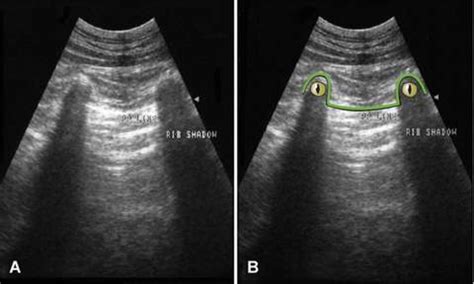

In the context of lung sonography, B Lines Ultrasound patterns are defined as discrete, laser-like vertical hyper-echoic reverberation artifacts. They arise from the pleural line and extend to the edge of the screen, moving in synchrony with lung sliding. Unlike A-lines, which represent normal horizontal reverberations caused by air-tissue interfaces, B-lines signify that the subpleural interlobular septa are thickened by fluid, cells, or fibrous tissue.

When these septa become edematous or infiltrated, they create an acoustic impedance mismatch that traps the ultrasound beam, resulting in the characteristic vertical "comet tail" appearance. Because they move with the visceral pleura, their presence is a highly sensitive marker for the loss of lung aeration.

To accurately assess for B Lines Ultrasound artifacts, clinicians should utilize a high-frequency linear probe for better resolution of the pleural line, or a curvilinear probe for deeper penetration. The patient should be evaluated in the supine or semi-upright position, scanning across multiple zones of the thorax.

1. Place the probe perpendicular to the ribs in an intercostal space.

2. Identify the pleural line—the hyperechoic line moving between the two ribs.

3. Observe the movement of the pleura (lung sliding) to ensure proper positioning.